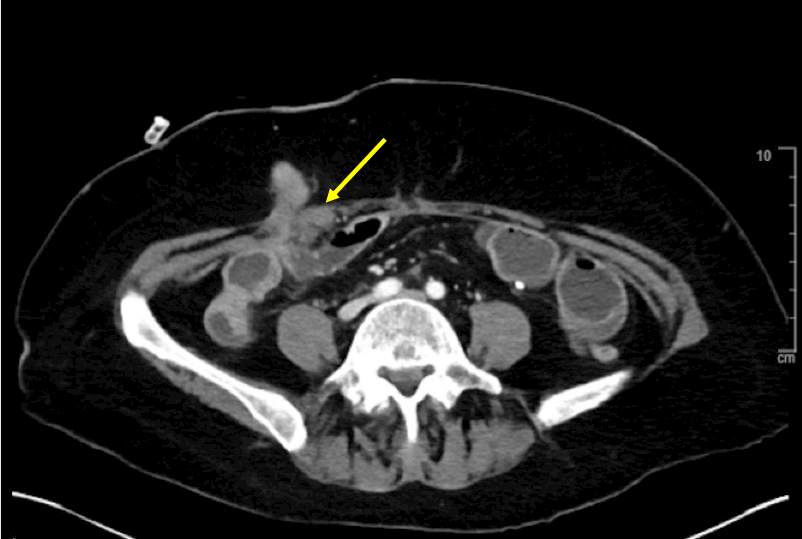

Admission CT

CT performed on initial presentation to the hospital showing metastic nodule causing an obstruction at the level of the fascia.

CT performed on initial presentation to the hospital showing metastic nodule causing an obstruction at the level of the fascia.

Fluoroscopic image after the placement of lumen apposing metal stent in the ileum across the extrinsic stricture.Admission CT

CT performed on initial presentation to the hospital showing metastic nodule causing an obstruction at the level of the fascia.

CT performed on initial presentation to the hospital showing metastic nodule causing an obstruction at the level of the fascia.